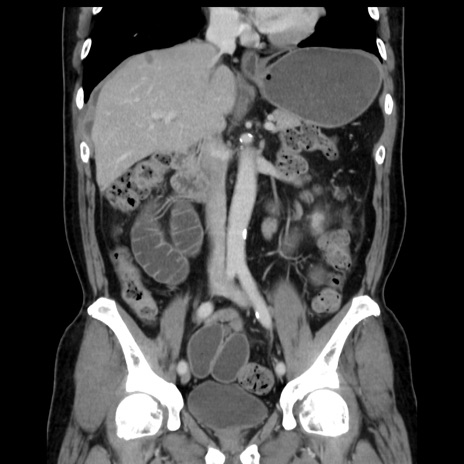

症例16(冠状断像)

【症例】 70歳代男性

【主訴】 腹痛、嘔吐

【現病歴】 約1ヶ月前より間欠的に腹痛と嘔吐あり、当院消化器内科を受診したところCTで多発する肝臓のLDAを指摘され、精査中であった。以降は消化器症状は安定していたが、2日前より嘔気と腹痛があり、同日より排便・排ガスが消失した。改善認めず、 本日、救急外来を受診した。

【既往歴】 大腸ポリープ切除後。

【身体所見】意識清明・会話良好、BT 36.3℃、BP 127/80mmHg、 P 80bpm、腹部:膨満あり、平坦・軟、上腹部正中および下腹部正中に圧痛あり、反跳痛なし、筋性防御なし。

【データ】WBC 7200、CRP 0.77